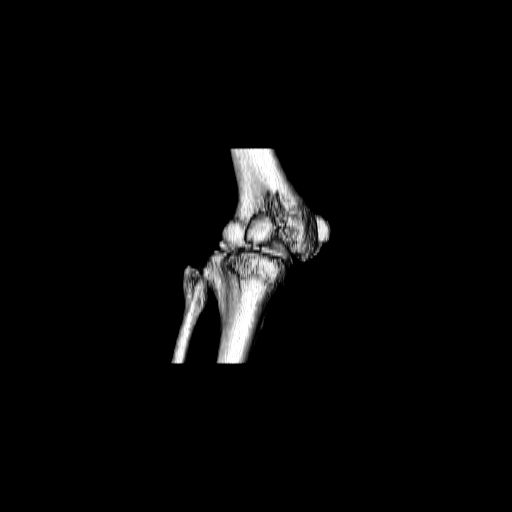

При внутрисуcтавных переломах трехмерные (3D) изображения, кроме красивого снимка, не дают полную информацию о состоянии отломков, самыми информативными являются корональные срезы на КТ и обычная длинная ренгенограмма конечности для сравнения оси конечности.

Фронтальные внутрисуставные переломы мыщельков бедра, так называемые Hoffa fracture, не частые, но встречающиеся переломы, в основном они связаны с травмой высокой энергией.

В зависимости от смещения рекомендуется сопоставление костных фрагментов с последующей жесткой фиксацией.

Даже при сросшемся переломе мыщелка рекомендуется реконструктивная операция для предотвращения последующих варус или вальгус деформации.